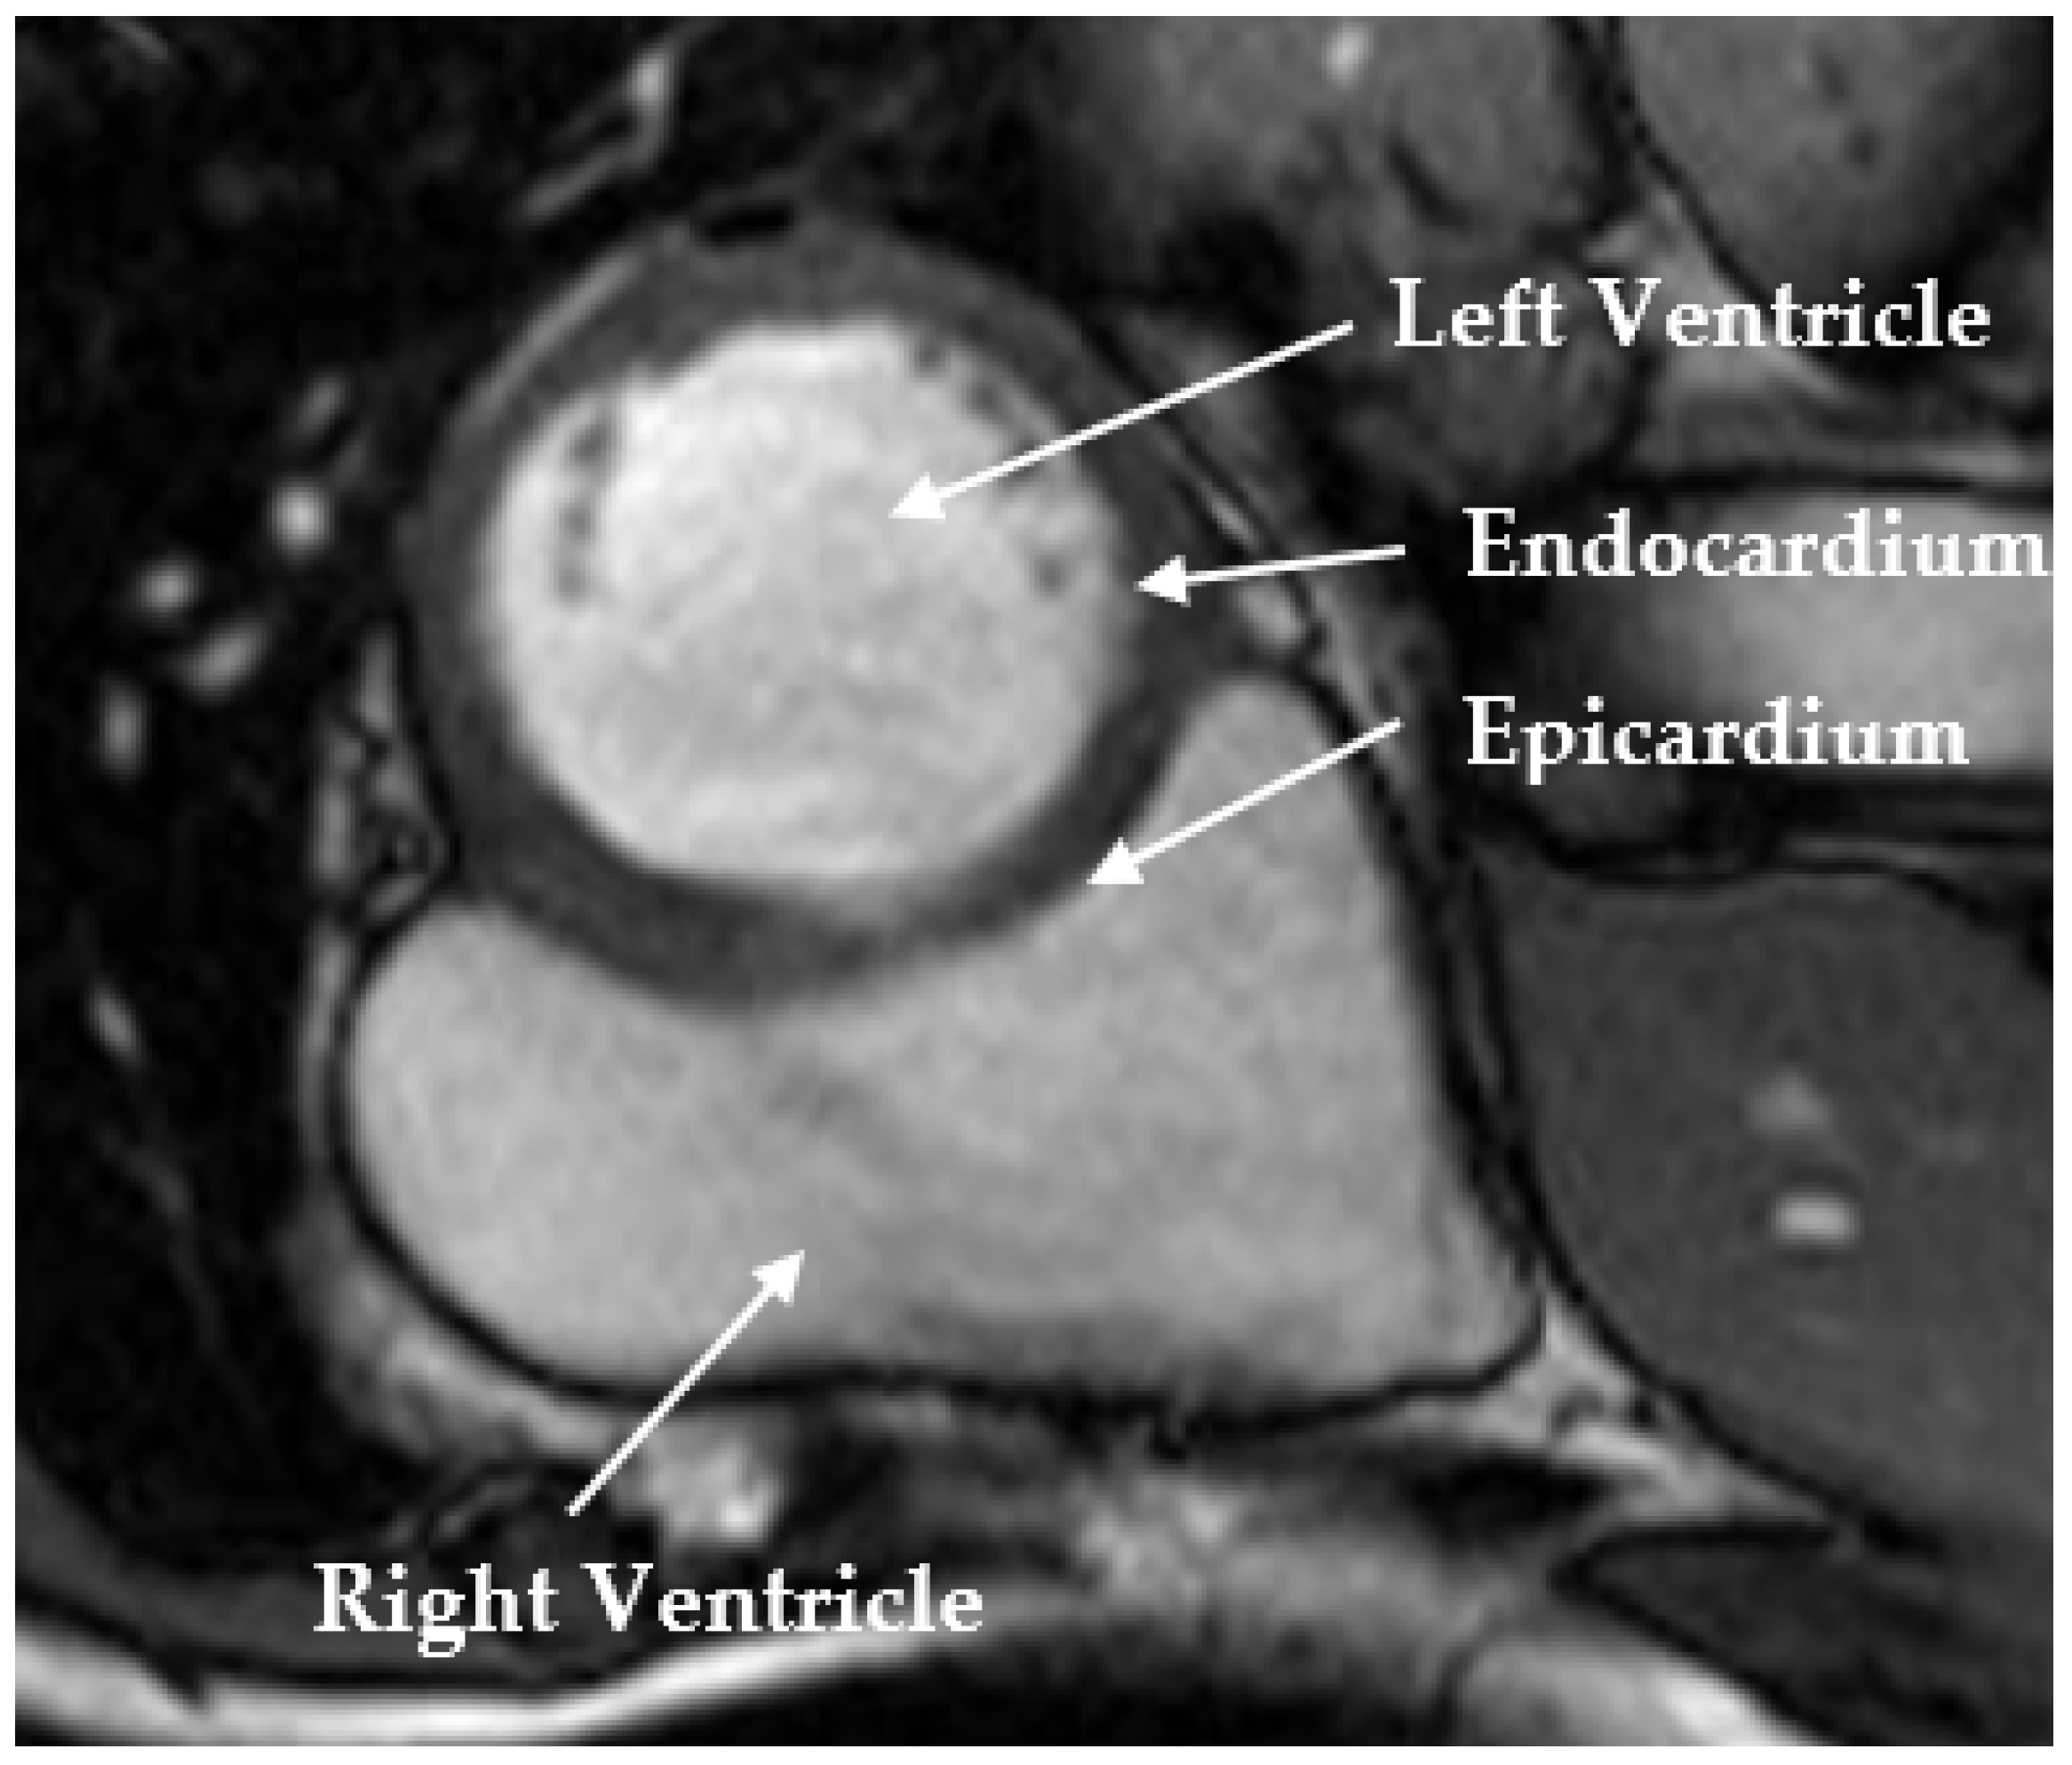

Combining UNet 3+ and Transformer for Left Ventricle Segmentation via Signed Distance and Focal Loss

3.1. Datasets